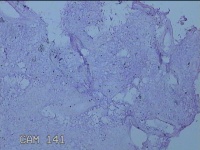

子宫腔内容物

性别

女

年龄

31岁

临床诊断

药流不全 子宫内膜炎待查

一般病史

药流术后1月。

标本名称

大体所见

灰白暗红色不规则碎组织1.5x1.3x0.3cm一堆,未发现明显的绒毛样组织。